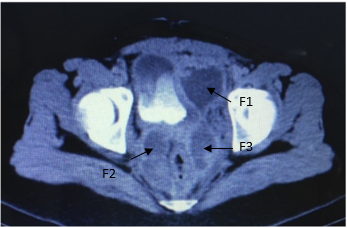

Al cuarto día postparto la paciente relata dolor en FII sin alteraciones en el transito urinario o digestivo. Al examen febril 38,5 ºC. Abdomen: blando, depresible, se palpa tumoración dolorosa en FII sin elementos de irritación peritoneal. El hemograma presenta glóbulos rojos 3.56mill/µL, hemoglobina de10.2 g/dL, hematocrito 31.9 %, 20.3mil/µL glóbulos blancos, plaquetas 384000/mL. Proteína C reactiva 91 mg/L.Función renal, hepática y crasis normales. Se solicita ecografía transvaginal que informa: Útero de 156 mm de longitud por 72 mm transverso y 85 mm antero posterior. En cara posterior izquierda una imagen heterogénea de 99 mm por 51mm, compatible con hematoma. Para valorar extensión del mismo se complementa con resonancia magnética (RM) abdomino pélvica que informa: útero aumentado de tamaño de 193 mm diámetro longitudinal sin imágenes patológicas en cavidad uterina. Colección en pelvis menor, a nivel de fosa ilíaca izquierda de 138mm longitud por 70 mm transverso por 68 mm antero posterior sin realce con contraste y en continuidad con ésta dos imágenes, una pararectal izquierda de 70mm de longitud por 33mm transverso y 66 mm anteroposterior, la otra en espacio pararectal derecho de 48mm de longitud por 28mm transverso y 70mm anteroposterior. (Figura I y II). En suma: hematomas subagudos subperitoneales en FII y a ambos lados del recto. Ante la evolución desfavorable y con planteo de hematoma del ligamento ancho complicado por proceso infeccioso se opta por laparotomía exploratoria y terapéutica. En el intraoperatorio se visualizan múltiples hematomas subperitoneales y en el ligamento ancho izquierdo que se evacúan, no sangrado activo, se realiza lavado del lecho y se coloca drenaje por contra abertura. (Figura III). La paciente se retira estable del block quirúrgico, se instaura nuevo plan antibiótico en base a Imipenem 500mg cada 6 hs i/v. Evoluciona favorablemente sin dolor ni síndrome toxoinfeccioso, no alteración en los tránsitos, genitorragia escasa. A los 30 días se otorga alta con tomografía computada de abdomen y pelvis que evidencia reducción de colecciones mayor al 50%. Seguimiento en primer nivel de atención clínico e imagenológico con alta a los 60 días posparto con resolución total de colecciones.

Figura I. RM. Hematoma de ligamento ancho: colección en fosa ilíaca izquierda (flecha 1 - F1), para rectal derecha (flecha 2- F2) e izquierda (flecha 3- F3).